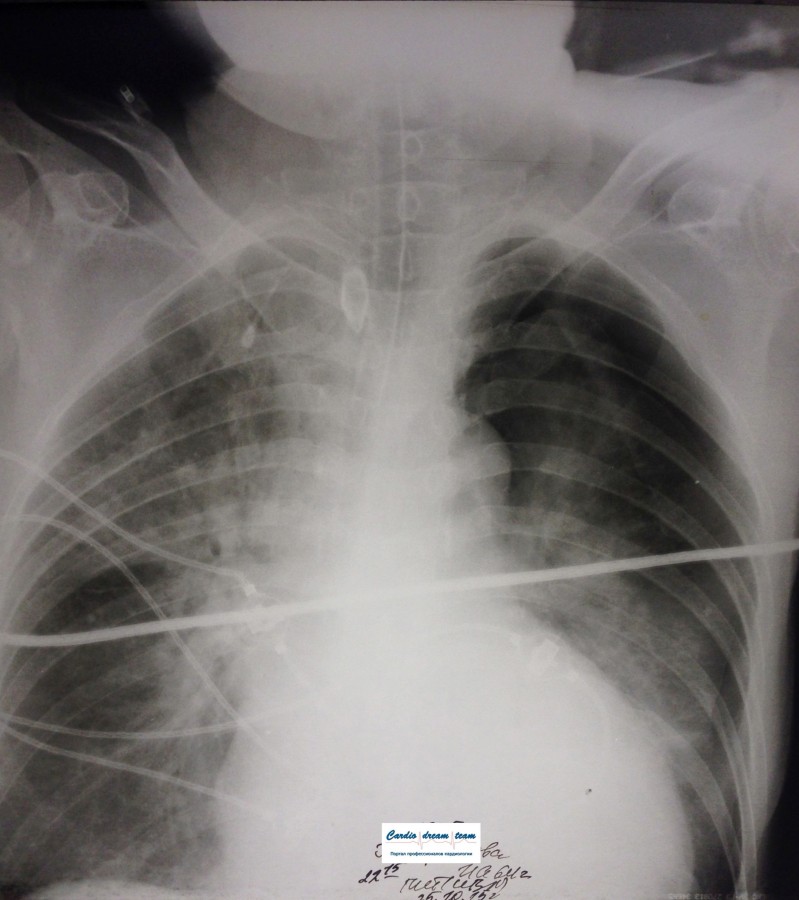

Проведена рентгенография органов грудной клетки в прямой проекции, положение полусидя, условия ПИТ, Р-контроль Легочные поля: Отрицательная динамика: правое легкое поджато к корню. Тень средостения резко смещена влево. Выраженная подкожная эмфизема мягких тканей грудной клетки справа. Тень подключичного катетера в проекции ВПВ. Легочный рисунок: диффузно деформирован за счет пневмосклероза, сгущен справа Корни: тень средостения смещена влево Синусы: нечеткие Сердце: широко лежит на диафрагме (позиционно) ЗАКЛЮЧЕНИЕ: Правосторонний пневмоторакс, отрицательная Р-динамика. Эмфизема мягких тканей грудной клетки. Пневмосклероз. Р-контроль.